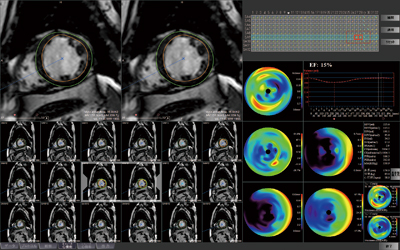

MRIの通常の検査では、頭部、脊椎系の件数が多く、ほかに乳腺、心臓、肝臓、前立腺などを行う。新病院では、心臓センターと連携してMRIによる心臓解析に本格的に取り組む体制を整え、心臓検査に対応したMRIを導入し3DWSにも心臓解析機能を搭載した。心臓MRI検査では、心筋症や急性心筋梗塞のPCI後のフォローアップでMRIによる造影検査を行い、ziostation2による心臓解析を行っている。心筋の機能解析では、左室解析を行うためのシネ撮像、T2のblack blood、安静時のパフュージョン、遅延造影(LGE)を行うが、このうちシネとLGEによる心筋障害の解析をziostation2のMR心機能解析2で行っている。中主任は、MR心機能解析について、「スムーズに解析できています。心筋の内膜と外膜のトレースについても、輪郭線の自動抽出の精度が高く、素早く処理できます。解析など処理にかかる時間も速く、1日に複数の解析を行う場合にも助かっています」と言う。

さらに、「画像診断にも定量評価が求められるようになっていますが、左室機能解析ではブルズアイマップでAHAに準拠した17セグメントに分類し、セグメントごとに壁厚や壁運動を数値で計測することができます。遅延造影の情報とあわせて提供することで臨床科から評価いただいています」とziostation2によるMR心機能解析に期待する。

■ MR心機能解析2による心機能解析

![]() MR心機能解析2のシネMR画面 |

![]() PhyZiodynamicsの技術を取り入れ精度の高い壁の自動抽出を行う(左)。 17セグメントによるブルズアイマップ(右) |